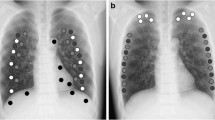

Chest radiographs (CXRs) of forty adult patients were obtained with the two X-ray devices, one with DES and one with bone suppression software. Three image quality metrics (relative mean absolute error (RMAE), peak signal-to-noise ratio (PSNR), and structural similarity index (SSIM)) between original CXR and BSI for each of D-BSI and S-SBI groups were calculated for each bone and soft tissue areas. Two readers rated the visual image quality for original CXR and BSI for each of D-BSI and S-SBI groups. The dose area product (DAP) values were recorded. Paired t test was used to compare the image quality and DAP values between D-BSI and S-BSI groups.

In bone areas, S-BSIs had better SSIM values than D-BSI (94.57 vs. 87.77) but worse RMAE and PSNR values (0.50 vs. 0.20; 20.93 vs. 34.37) (all p < 0.001). In soft tissue areas, S-BSIs had better SSIM values than D-BSI (97.56 vs. 91.42) but similar RMAE and PSNR values (0.29 vs. 0.27; 31.35 vs. 29.87) (all p < 0.001). Both readers gave S-BSIs significantly higher image quality scores than D-BSI (p < 0.001). The mean DAP in software-related images (0.98 dGy·cm2) was significantly lower than that in the DES-related images (1.48 dGy·cm2) (p < 0.001).

Bone suppression software significantly improved the image quality of bone suppression images with a relatively lower radiation dose, compared with dual-energy subtraction technique.

• Bone suppression software preserves structure similarity of soft tissues better than dual-energy subtraction technique in bone suppression images.

• Bone suppression software achieves superior image quality for lung lesions than dual-energy subtraction technique in bone suppression images.